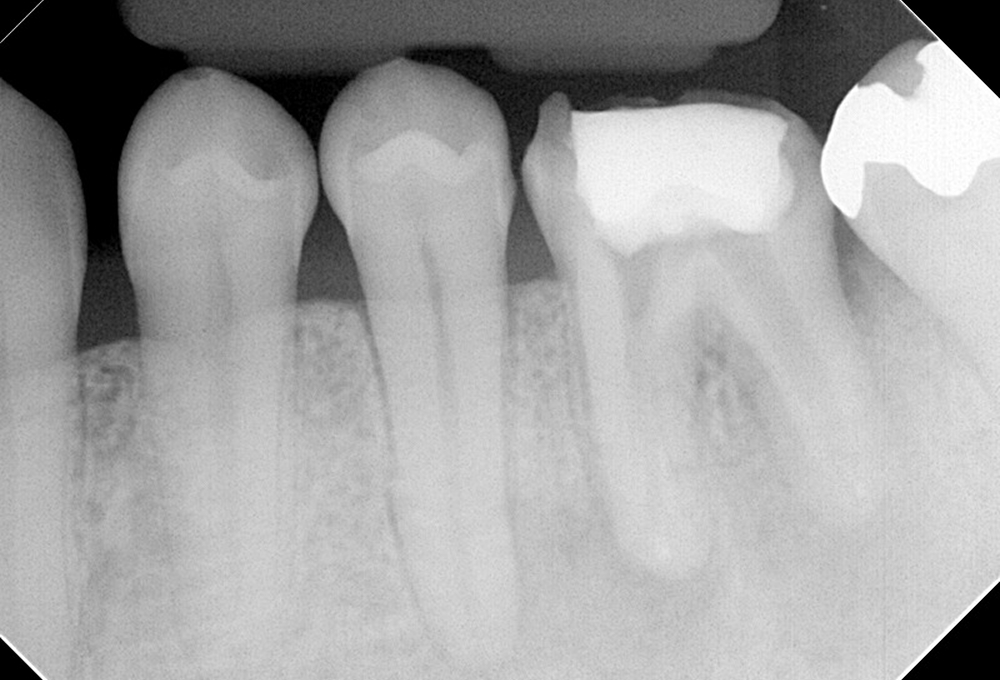

①左上7感染根管